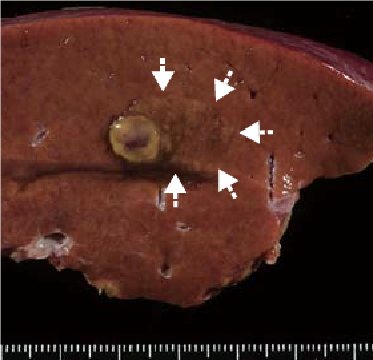

Macroscopic observation of resection samples

The tumors in the anterior segment were one that was 1 cm in diameter, with a swollen sectional surface, and one that was 2 cm in diameter, had indistinct margins, and was a somewhat different color from the surrounding non-cancer hepatic tissues (the S6 findings are shown on p. 7).

Histopathology findings

- (1)The nodular region with indistinct margins, to the right side of the simple nodule, was a region of early-stage HCC, and “a” shows the capsule of the simple nodule.

- (2)Inside the capsule there was HCC with a thick, moderately differentiated, cord-like structure, and the capsule exterior also had a structure similar to the portal region, initially appearing like non-cancer tissue.